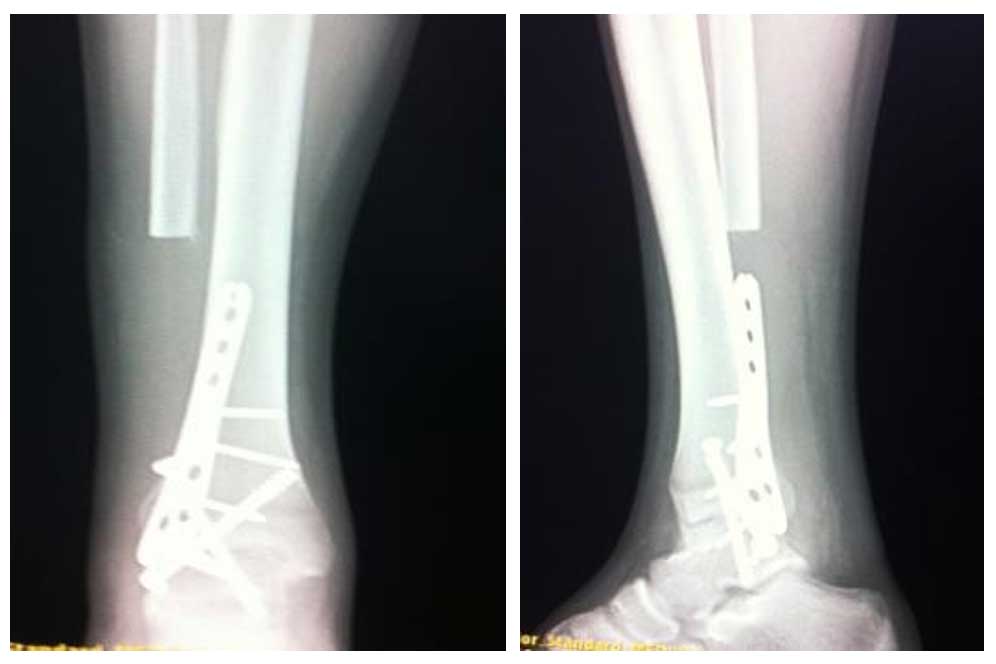

Ameliyat Sonrası: Röntgende distal fibula rezeksiyonu sonrası ayak bileği artrodez uygulanımı görülmekte.